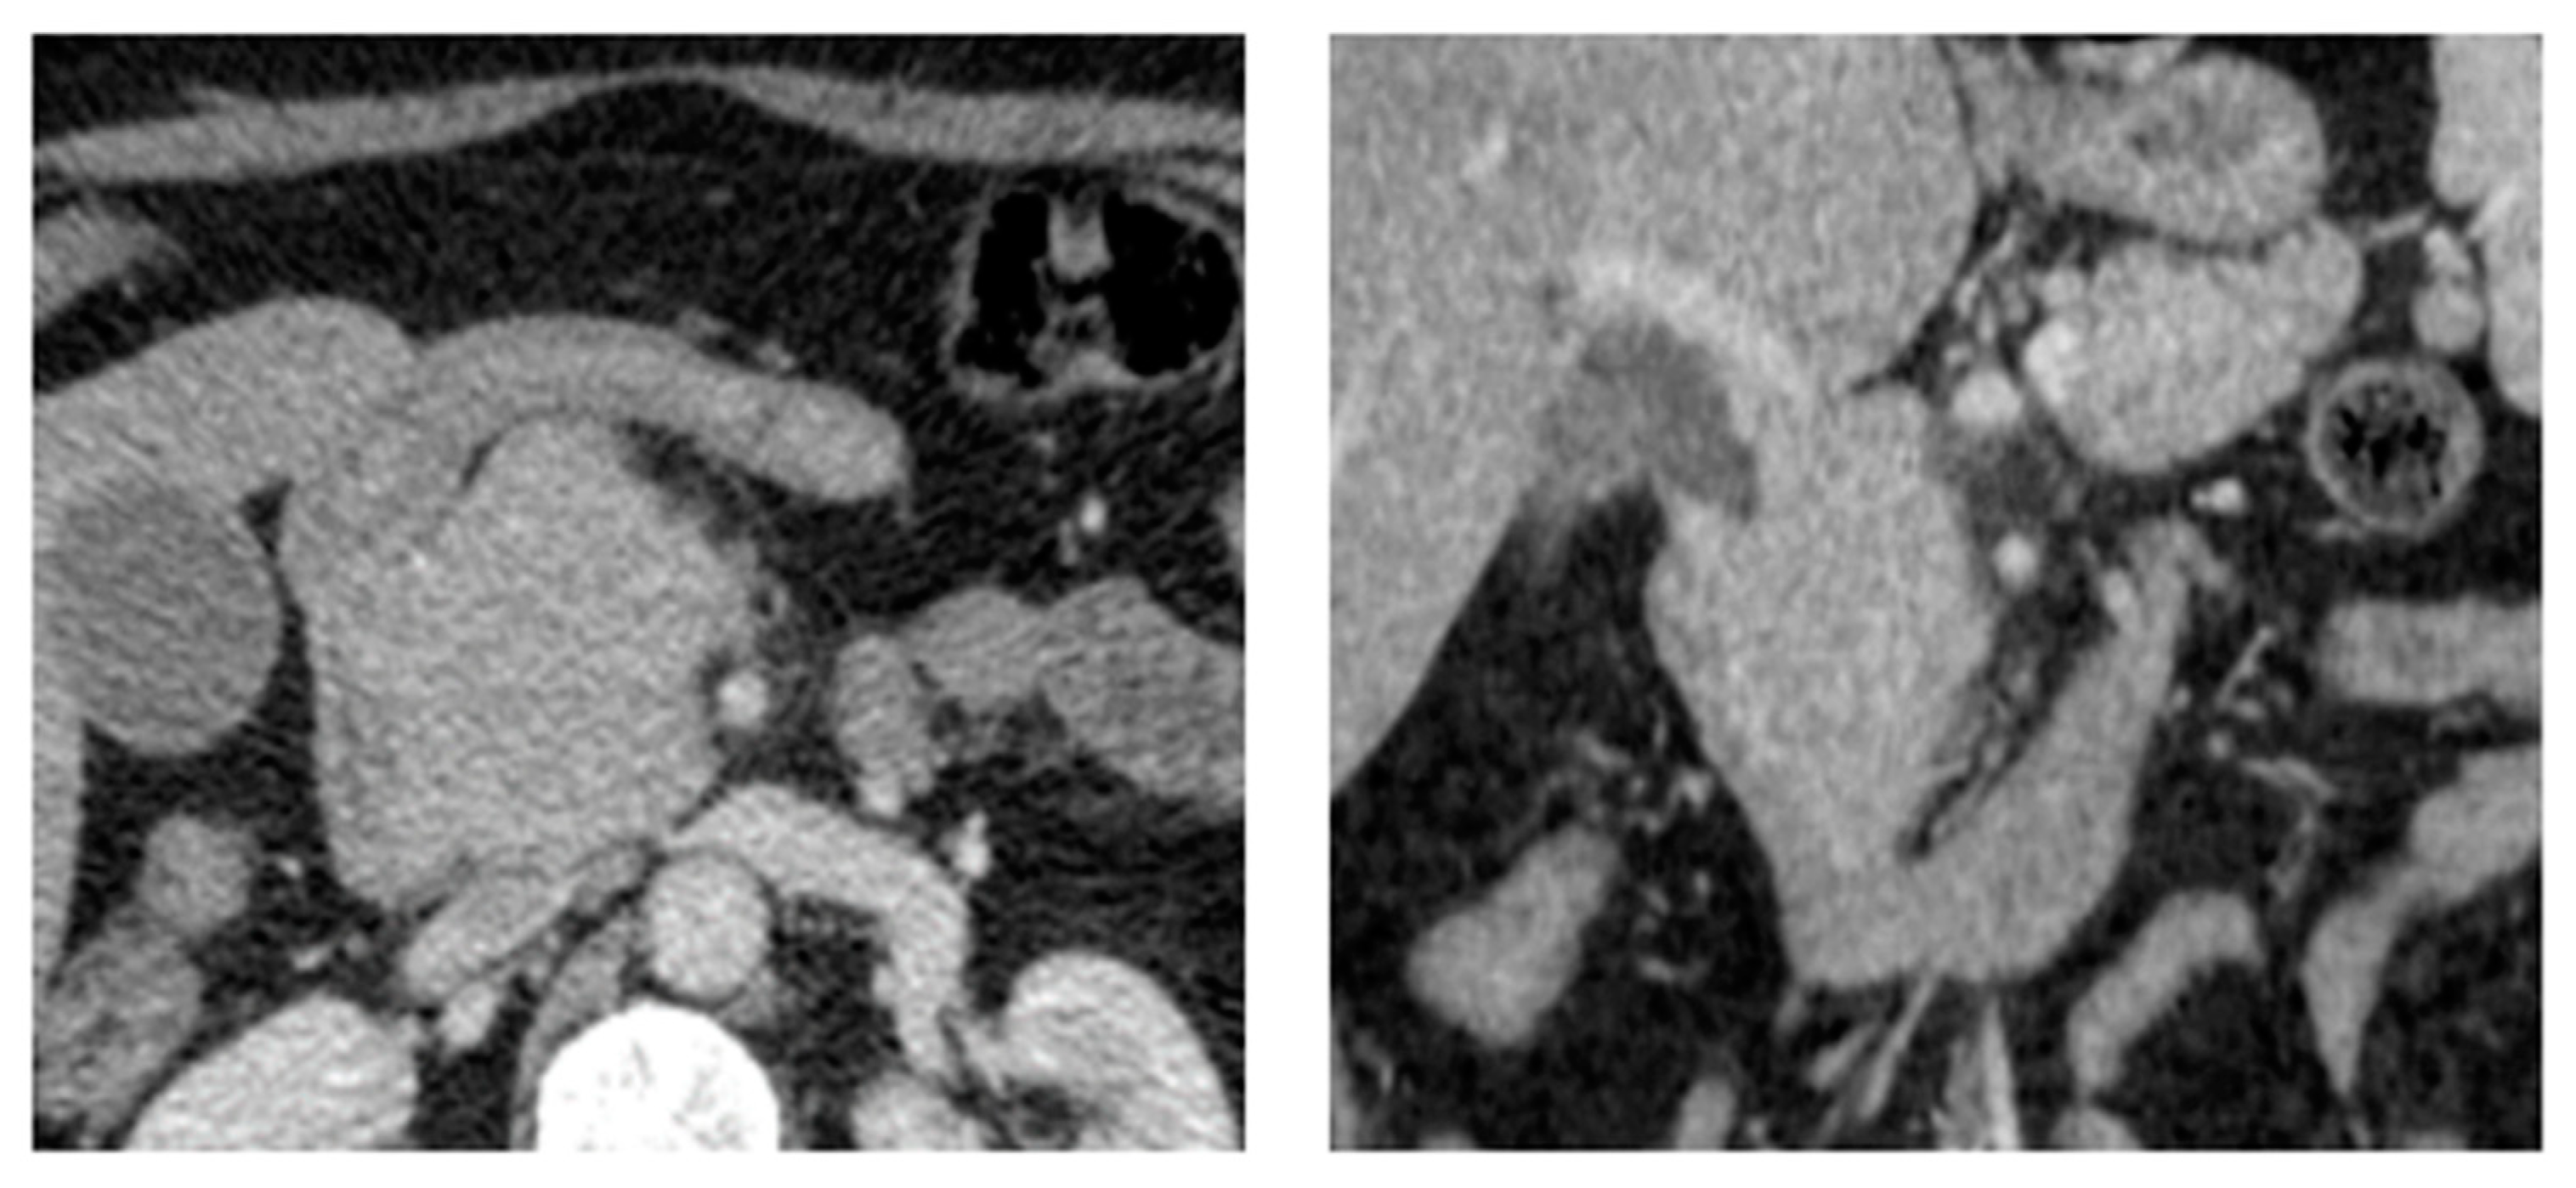

6. Pancreas

- Gupta, P.; Rice, G.D.; Abraham, K.; Ghole, V.; Ketkar, M. Extramedullary plasmacytoma of the pancreas and jejunum. Clin. Imaging 2009, 33, 240–243. [Google Scholar] [CrossRef]

- Kim, J.H.; Paik, W.H.; Joo, M.; Kim, J.G.; Kim, J.W.; Bae, W.K.; Kim, N.H.; Kim, K.A.; Lee, J.S. Extramedullary plasmacytoma mimicking pancreatic cancer: A case report and literature review. Endosc. Ultrasound 2017, 6, 269–272. [Google Scholar] [PubMed]

- Smith, A.; Hal, H.; Frauenhoffer, E. Extramedullary plasmacytoma of the pancreas: A rare entity. Case Rep. Radiol. 2012, 2012, 798264. [Google Scholar] [CrossRef] [PubMed]

- Wang, X.; Xie, H.; Zhang, L. Multiple myeloma with onset of pancreas involvement: A case report. Medicine 2019, 98, e16567. [Google Scholar] [CrossRef] [PubMed]

- Hatem, M.; So, B.; Gray, R.; Wong, J. Plasmocytoma presented as pancreatic head mass. Radiol. Case Rep. 2015, 10, 81–87. [Google Scholar] [CrossRef] [PubMed]

- Le, M.; Surapaneni, B.K.; Jain, V.; Vinayek, R.; Dutta, S.K. Pancreatic Extramedullary Plasmacytoma Presenting as a Pancreatic Mass. Clin. Med. Insights Gastroenterol. 2018, 11, 1179552218801603. [Google Scholar] [CrossRef] [PubMed]

- Rizk, R.C.; Weisberg, E.M.; Fishman, E.K. Solitary plasmacytoma of the pancreas: A rare case report. Radiol. Case Rep. 2024, 19, 1806–1809. [Google Scholar] [CrossRef] [PubMed]